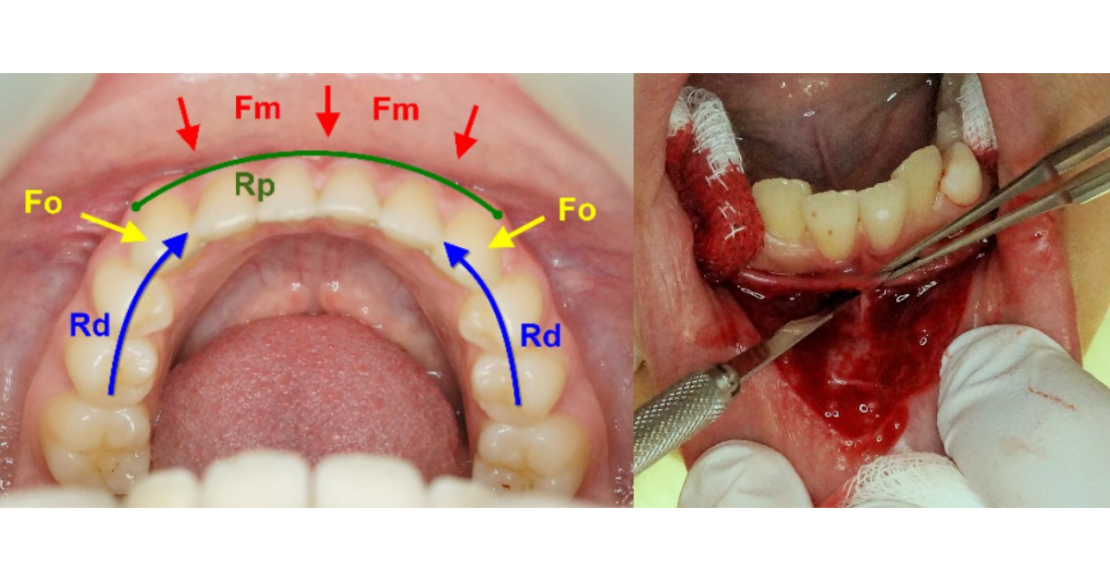

Plusieurs forces agissent sur cette région :

- Les forces musculaires (Fm) du complexe labio-mentonnier. Elles sont essentiellement centripètes et s’étendent comme les insertions musculaires de la canine à la canine.

- Les forces occlusales (Fo) avec les incisives et canines maxillaires. Egalement centripètes, elles sont en plus d’être verticales, sagittales en incision, et plus transversales en mastication

Elles rencontrent deux résistances :

- La résistance mécanique du complexe dentaire (Rd), ou sa capacité à résister au déplacement

- La résistance mécanique du parodonte (Rp), dépendante du biotype parodontal

Ce système mécanique forme une arche dans laquelle les dents sont l’armature, le parodonte le liant et les forces musculaires et occlusales la charge mécanique à soutenir. Ce système est donc comparable à celui d’une arche en architecture (figure 2a et b).

Situations mécaniques possibles :

- Rd ≥ (Fm + Fo) et Rp ≥ (Fm + Fo) : situation d’équilibre

- Rp ≥ (Fm + Fo) > Rd : déséquilibre mécanique avec conséquences dentaires

- Rd ≥ (Fm + Fo) > Rp : déséquilibre mécanique avec conséquences parodontales

- (Fm + Fo) > Rd et (Fm + Fo) > Rp : déséquilibre mécanique avec conséquences dentaires et parodontales

Figure 2 : similitude mécanique entre une arche (a) et la région incisivo-canine mandibulaire (b)